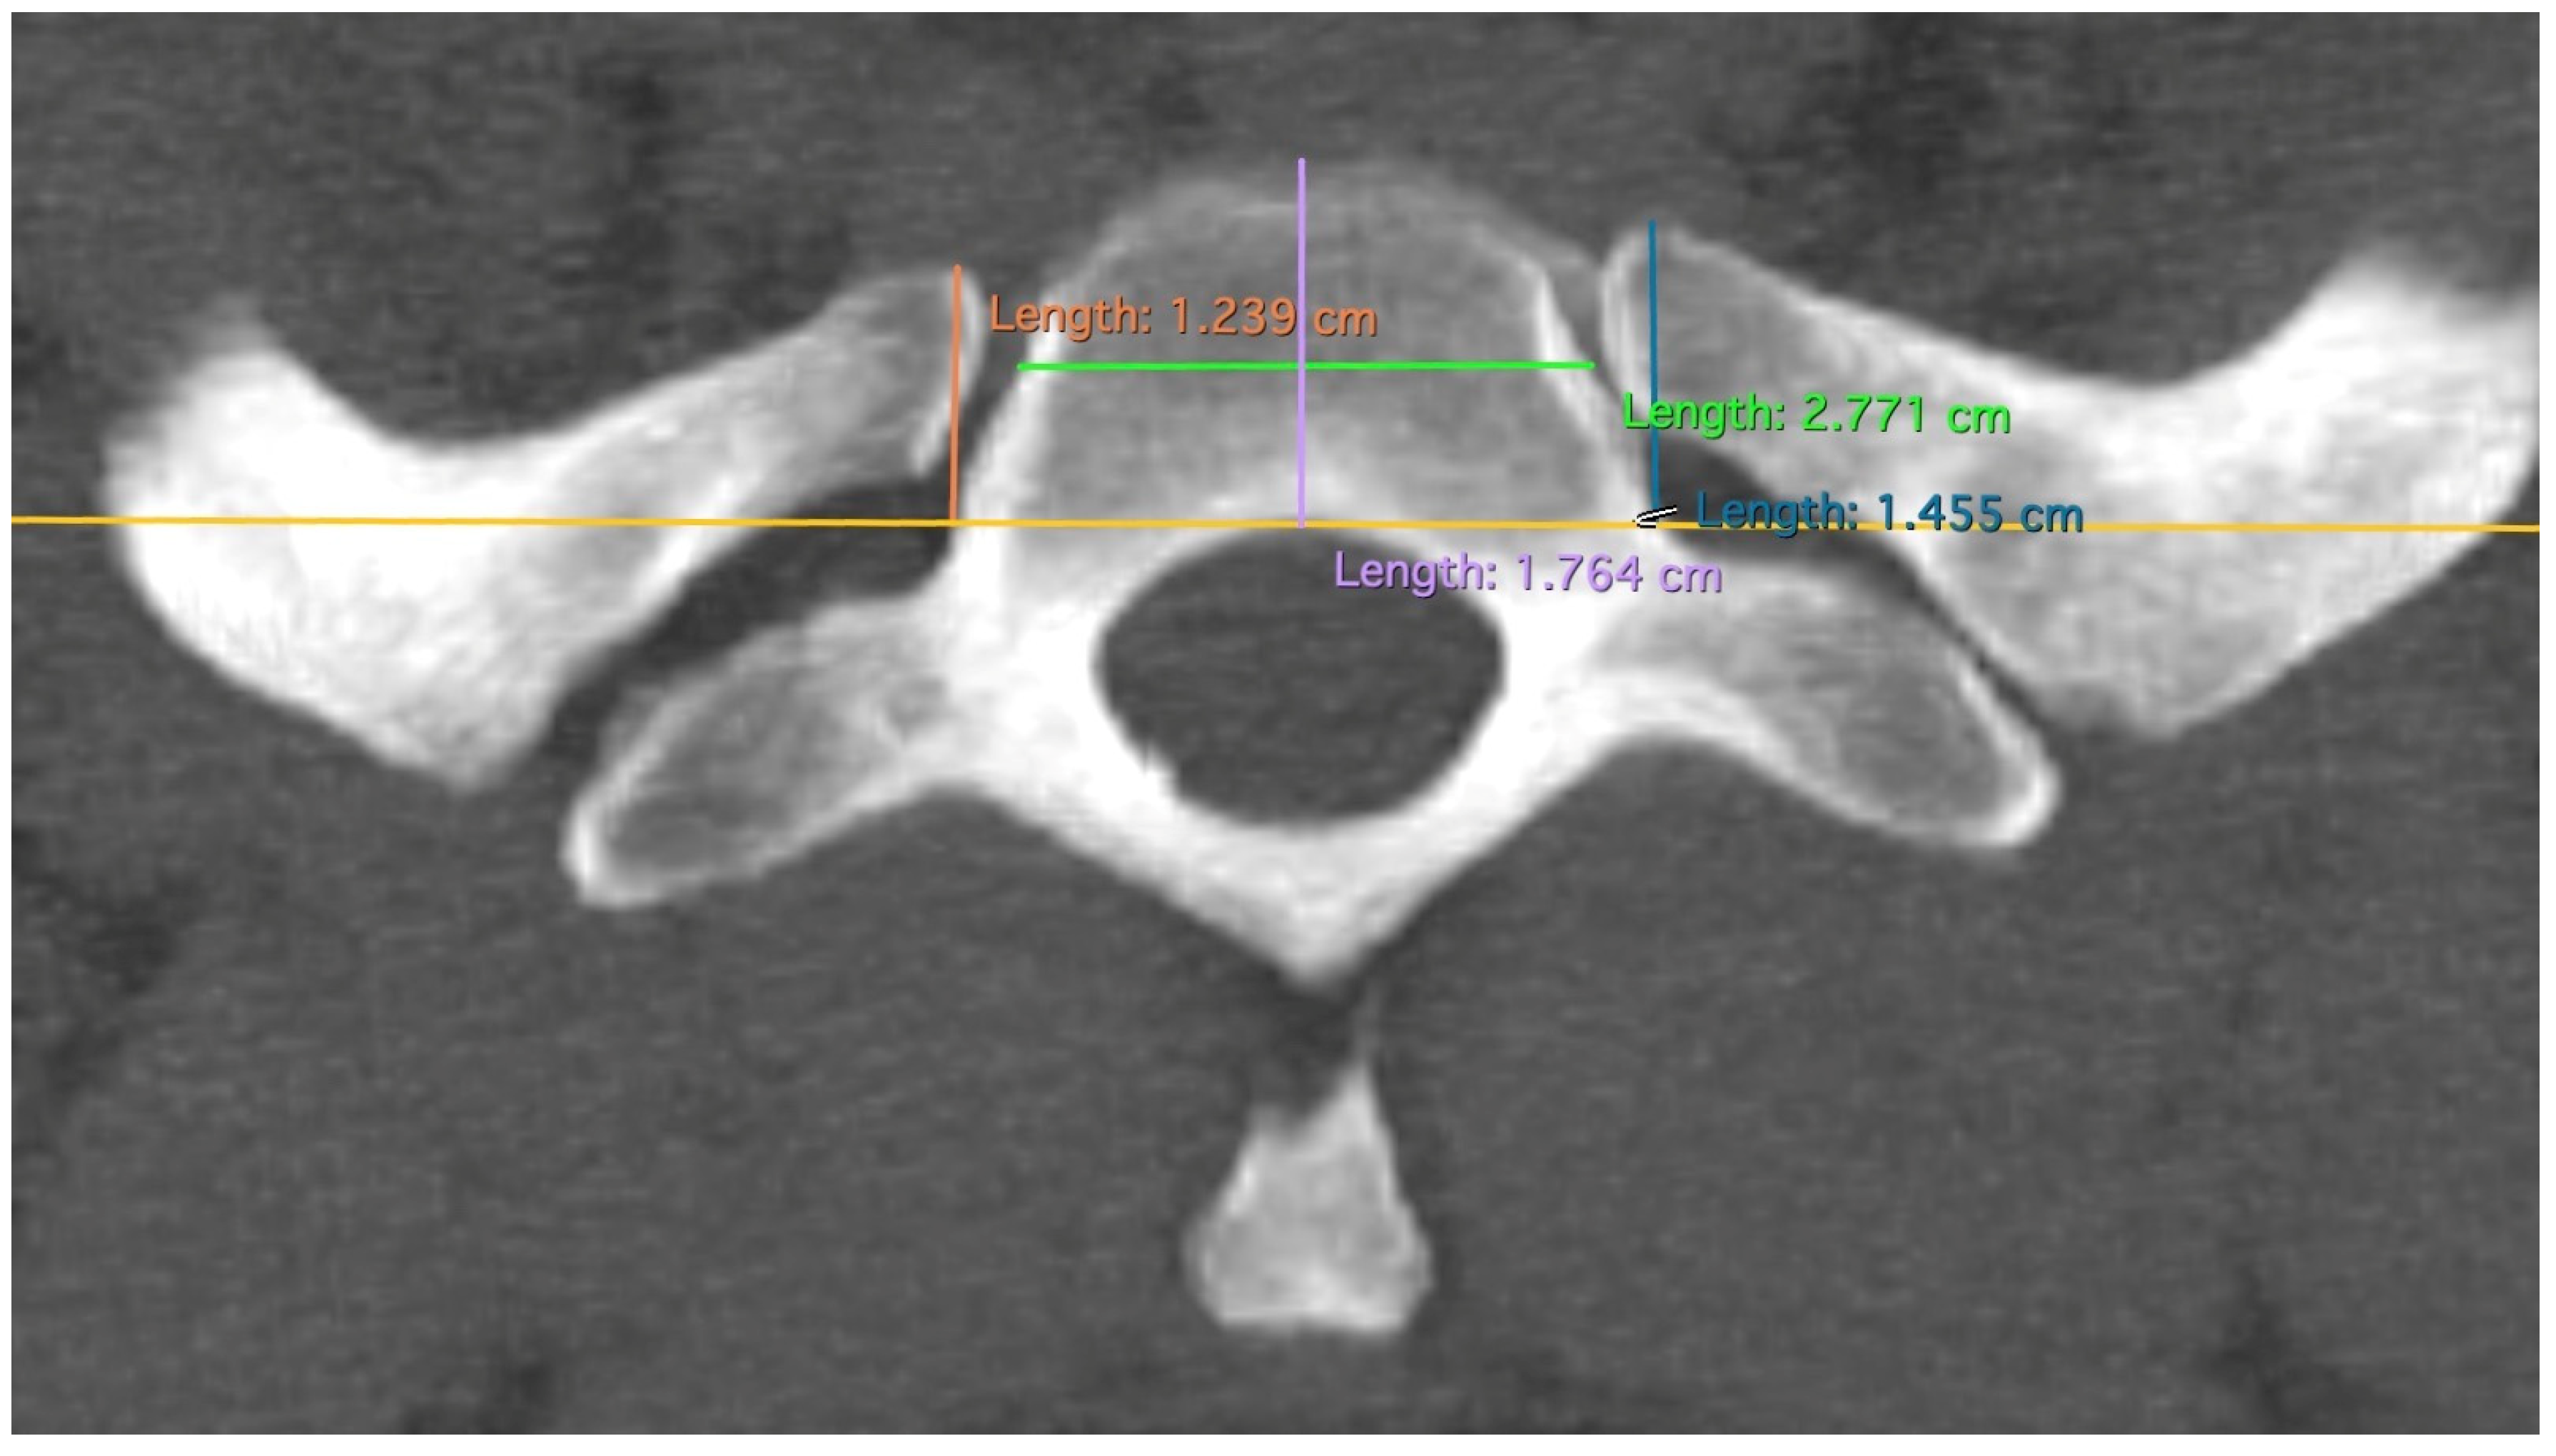

| Variable Name | Abbreviation | Description |

|---|---|---|

| Rib width | R | Minimal width of the rib at the height of the front edge of the first thoracic vertebral body. |

| Anterior to posterior rip extension | RAP | From the most ventral point of the caput costae 1, a perpendicular line to the tangent of the posterior edge of the first thoracic vertebral body. |

| Vertebral body width | VBW | Width of the first vertebral body at the level of the centre of the articulatio capitis costae 1 |

| Vertebral body depth | VBD | From anterior edge to posterior edge (most ventral point of vertebral foramen) of the first vertebral body |